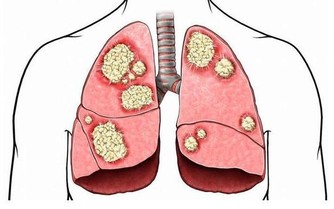

2.老煙槍清肺護肺煙越早戒越好

數據表明10個死於肺癌的患者中,9個是菸民在男性吸菸者中,一生肺癌發病風險為17.2%。而不吸菸者的風險僅為1.3%。對吸菸者來說清除肺部有害物質,首先要做的肯定是戒菸!

即便是不吸菸的人,也應多吃一些清肺的食物,如西藍花、芥藍、甘藍等十字花科的蔬菜,有助清除肺部有害細菌。同時,需注意的是,五臟中的肺對應五色中的「白色」。中醫以白色食物來清肺防燥,與肺同系統的器官有大腸、皮膚、喉嚨、支氣管等。所以,平日容易感冒,或是肺與支氣管常不舒服、易咳嗽的人,腸胃脆弱但又容易胖的人,膚色不佳的人,要多吃一些白色的食物,例如白蘿蔔、白菜、甘蔗等蔬菜,杏仁、山藥、百合和白芍等中藥材。